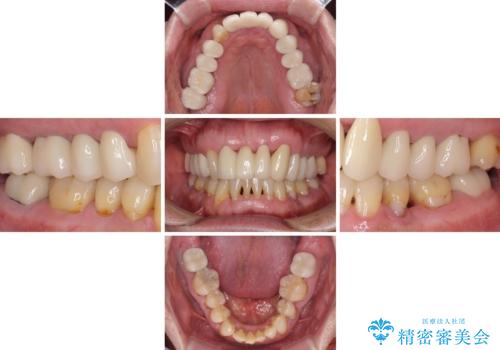

上の歯は見た目を良くしたいというご希望があったため、歯周外科処置を行った歯についてはセラミッククラウンで補綴することとしました。

気になっていた歯の痛みや歯肉からの出血がなくなり、改善したいと思っていた外見も綺麗に仕上がり、大変満足していただきました。